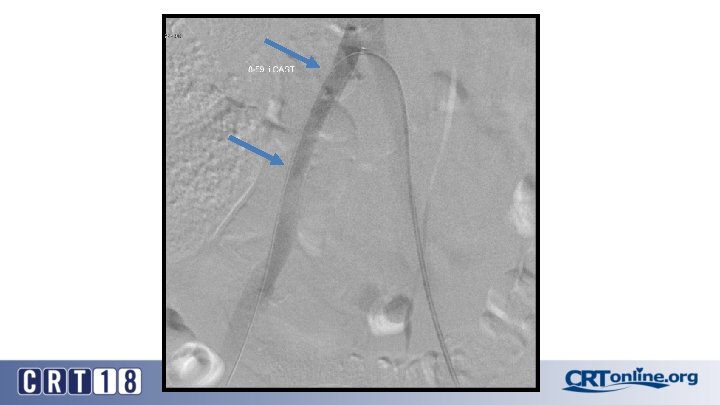

CS Compared to BMS in iliac occlusion • 2009 and December 2015, 128 iliac artery occlusions were stented • A CS was implanted in 78 iliac arteries (61%) and a BMS in 50 (49%) • After propensity score matching (lesion site and length separated and associated femoropopliteal disease included) (47 for each group). • Technical success was 98% • Complication rates same: 12% vs. 12%, p = 1. 0 • 30 day mortality rates same: 2% vs. 2%, p = 1. 0 Piazza M, et al. Outcomes of polytetrafluoroethylene-covered stent versus bare-metal stent in the primary treatment of severe iliac artery obstructive lesions. J Vasc Surg. 2015; 62(5): 1210 -8.

CS superior to BMS, in the right setting • At 36 months (average 23 ± 17) overall primary patency only approached significance: 87% vs. 66%, p =. 06 • For TASC D, CS: 88% vs. BMS: 54% (p =. 03) • Patency was in favor of CSs for occlusions > 3. 5 cm in length (p =. 04), total lesion length > 6 cm (p =. 04), and occlusion with calcification > 75% of the arterial wall circumference (p =. 01) • Kissing stent patency also superior with CS